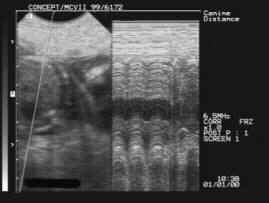

ULTRASOUND PREGNANCY DIAGNOSIS

Foetal heartbeats - day 42 Foetal sacs – day 28